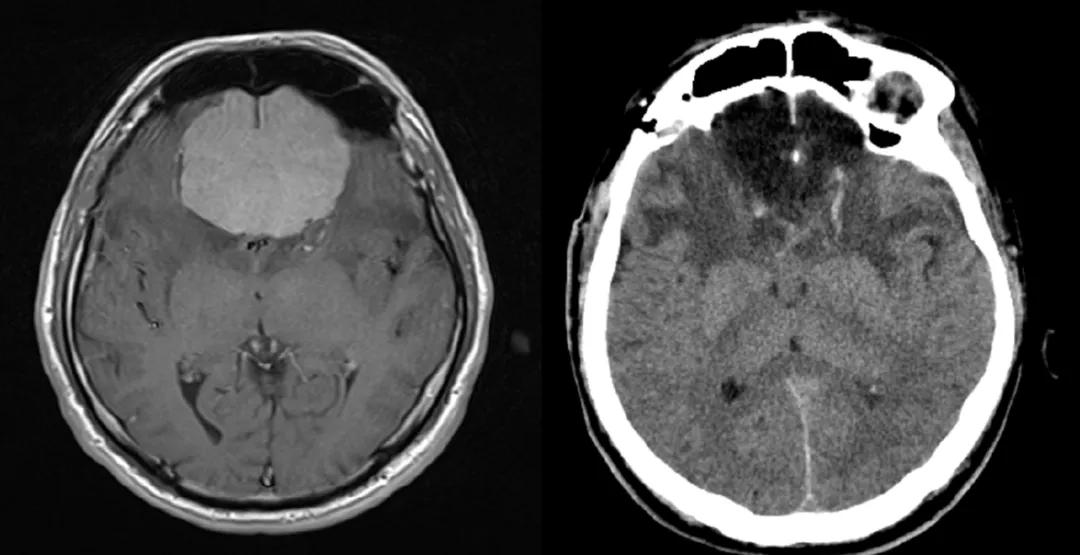

脑肿瘤发展进程如何?不及时手术切除能长多大?很多人对此并没有什么概念,你可以想象,中国成年人正常头围才54-58cm,而居然有人的脑瘤从左脑一直长到了右脑,最长直径达11cm,足足可以称霸脑瘤界!

白色高亮信号团块为肿瘤

2 脑膜瘤

恶化几率: 文献报道,脑膜瘤的平均生长速度大约是每年直径长1-2mm,每种肿瘤、每个人的肿瘤生长速度都是不一样的,而且也不是匀速生长。脑膜瘤有良恶性之分,一般良性的脑膜瘤手术切除干净后就可以达到完全治愈的目的,很少出现复发的情况。患者大可不必过于担心它会恶变,只要积极进行治疗,良性肿瘤恶性的几率非常小,当然有一些报导了放疗后可能诱发脑膜瘤的恶变。而恶性脑膜瘤的生长速度较快,没有包膜,界限也不明显清晰,通常呈浸润性生长且分化显示不良好,不及时治疗可能肿瘤侵犯压迫脑组织引起肢体瘫痪、面瘫、言语不利等可能。

治疗策略:手术切除是治疗症状性脑膜瘤的首选方法。现代日益精进的手术显微镜、神经导航技术、术中神经生理监测、术中成像等技术,使得手术成功率和治愈率大为提高。手术的目的是减轻症状和改变肿瘤的自然历程。对于恶性脑膜瘤术后、次全切术后、因各种原因失去手术机会或术后复发不宜再手术的患者可选择放疗。此外,也有多种化疗药物和分子靶向药物用于恶性脑膜瘤的辅助治疗提示可能有一定作用。

最佳手术时机:只要肿瘤占位压迫脑组织引起症状,能手术就需要尽早做手术,特别是那些生长速度较快、有明显症状的脑膜瘤,越早做手术越好。比如,发现脑膜瘤,半年后第一次复查时,发现肿瘤有明显增大,就应该及早手术。如果说第一次复查时没什么变化,第二、三次复查时,发现肿瘤明显增大了,尤其有症状情况下,要尽早手术。